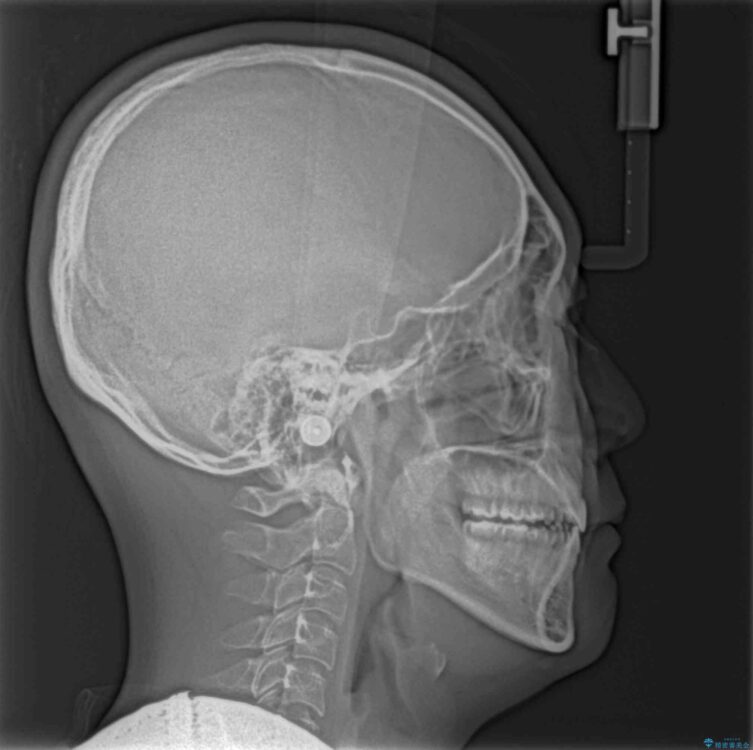

治療前

• 口元の突出感を改善 受け口傾向の咬み合わせの抜歯矯正 治療前画像

受け口傾向の咬み合わせと口元の突出感を気にして来院された患者様です。

受け口傾向特有の狭い上顎歯列であったため、歯列の拡大を補助装置で行い、下顎歯列全体を後方に移動させることとしました。

奥歯の咬み合わせを改善させた後、上下左右の小臼歯(下顎は残存乳歯)を計4本抜歯し、ワイヤー装置にて口元の突出感を改善しながら咬み合わせを整えることとしました。